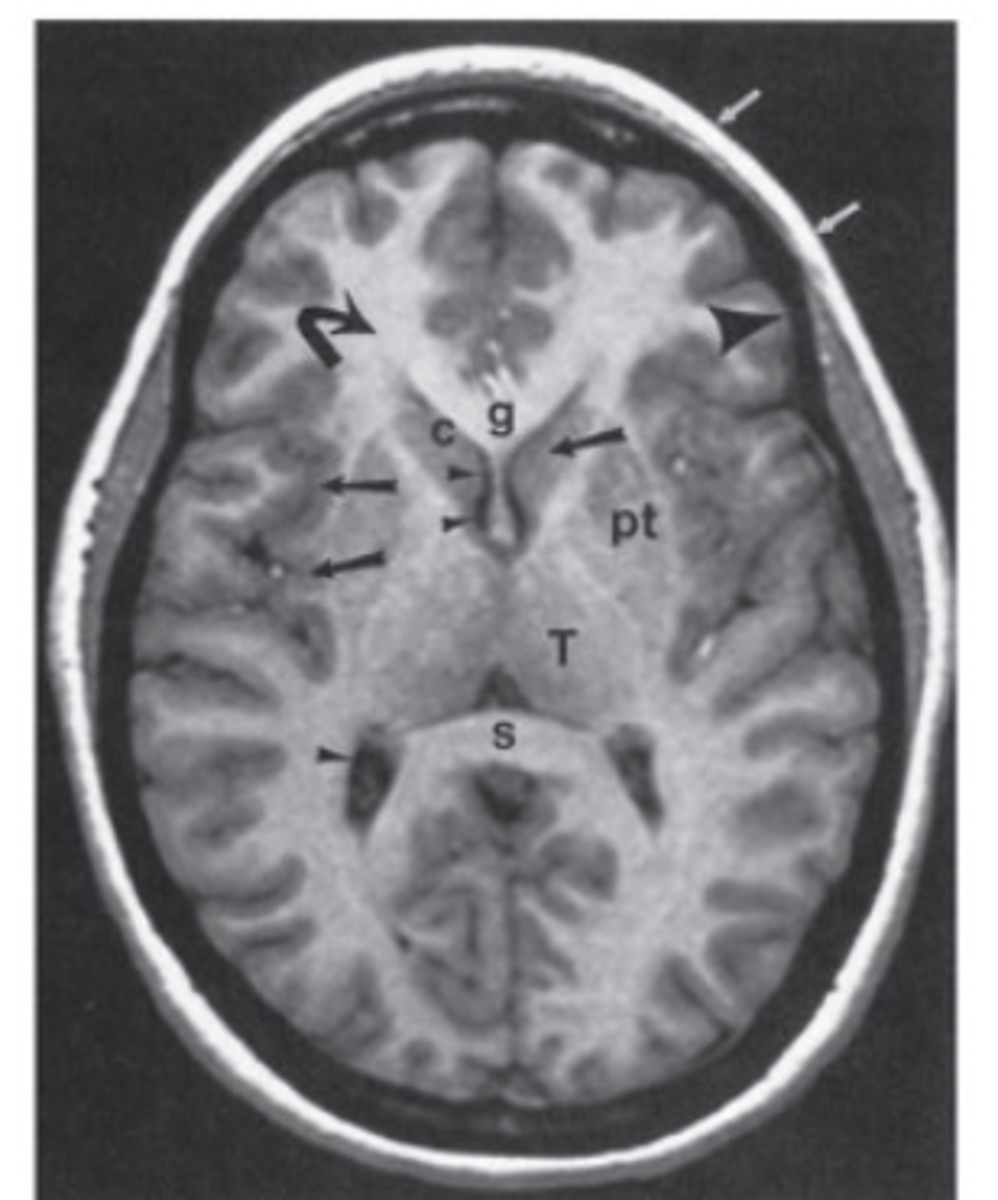

normal brain MRI